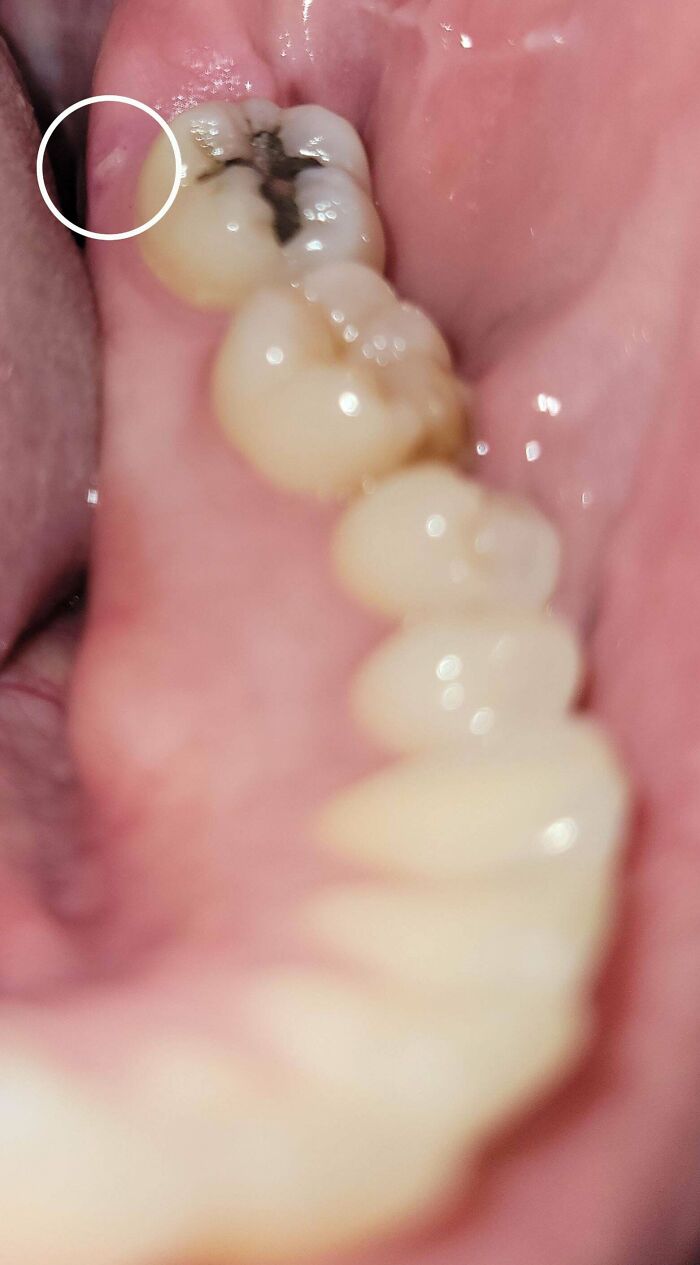

Heavy Calculus Removal

Look how squeaky clean the patient's upper teeth are FROM THE OUTSIDE. Probably only brushed "the visible part" 😱. Kids, brush your teeth everywhere.